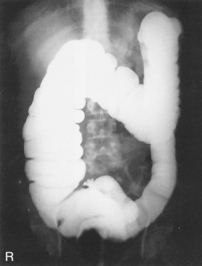

The air-barium distribution within the stomach and large intestine changes with various body positions. By knowing these distribution patterns, one can determine in which body position a radiograph was taken. Air always rises to the highest levels, and the heavy barium settles to the lowest levels (air is black, barium is white).

The ascending and descending portions are located more posteriorly, and thus more of these parts in general would be filled with barium (white) in the supine position and with air (black) in the prone position.

This much separation of barium and air occurs generally only with double-contrast barium-air studies.

Air-fluid levels would be seen in the erect position in which the air would rise to the highest position in each of the various sections of the large intestine, as shown in the accompanying figure.

Right and left decubitus projections (not shown on these drawings) also would demonstrate air-fluid levels, with air again rising to the highest portions.

Both right and left lateral decubitus are commonly taken as part of a double-contrast series.